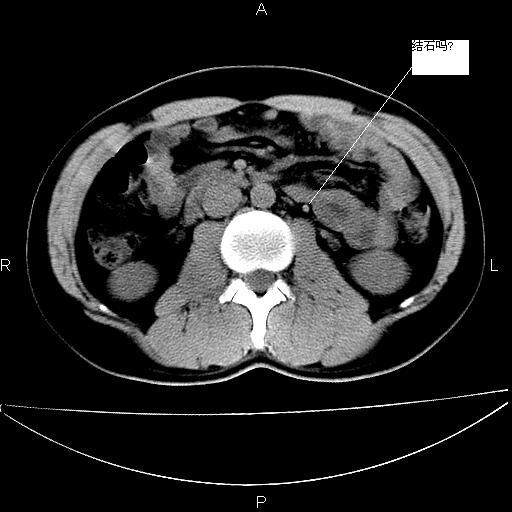

男 25岁 自述 尿频尿急,排尿困难20多天.无腰痛, b超说左肾盂轻度积水,左输尿管上端扩张.未见结石影. ct我看双侧肾盂轻度积水,双输尿管上端都扩张,大家看看能看见结石吗?

双输尿管扩张下端未见高密度结石和输尿管晕轮征,不好说是结石.增强后如何?

双肾轻度积水,未见明确结石,薄层对结石检出率较高。

未见明确输尿管结石,mru效果还好

双侧输尿管上端扩张,未见明确结石,可进一步ivp检查。